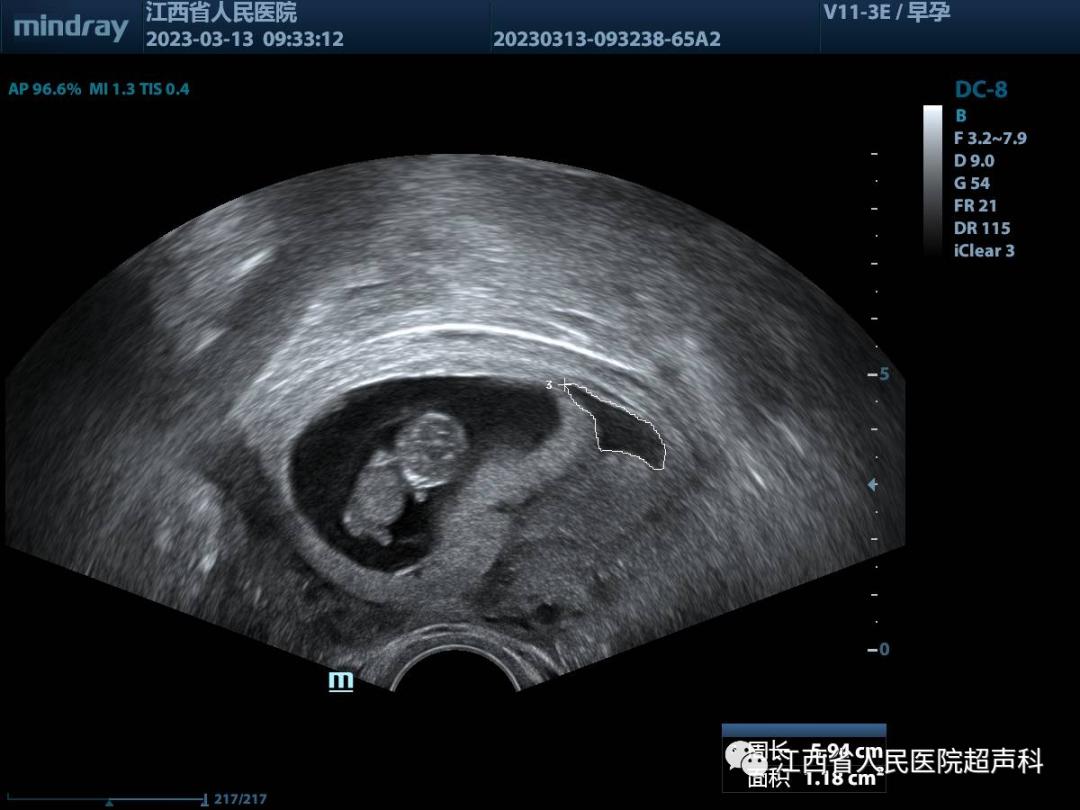

随着人们对健康的重视,许多宝妈一旦发现怀孕就会去做B超检查,有的时候会发现孕囊周围存在液性暗区,其实这个液性暗区就是孕囊旁的液体,一般是怀孕早期孕囊周边的出血或称为积液。

这种情况多属于植入性出血,说明孕囊与宫壁之间的缝隙里面有液体,大多数原因是孕囊在子宫中种植不稳,使得孕囊与子宫壁有些许剥离,导致孕囊周边积液,其量通常与出血量呈正相关。少量的孕囊旁积液绝大多数可以通过自身进行吸收,如积血量比较大,未被自身吸收,则可由阴道排出。